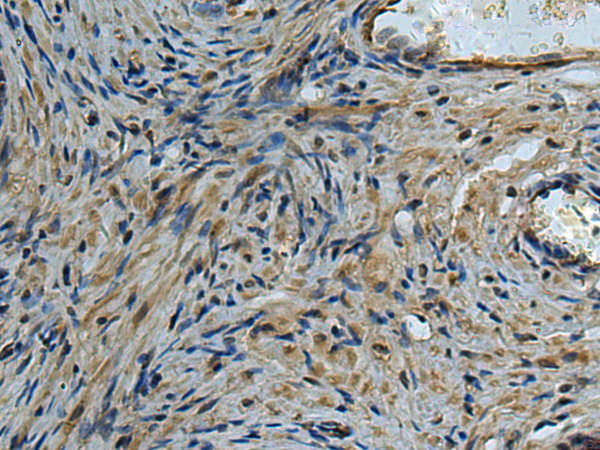

分类: 科研抗体货号: P08287别名: EPDR; UCC1; MERP1; MERP-1应用: WB,IHC反应种属: Human, Mouse, Rat